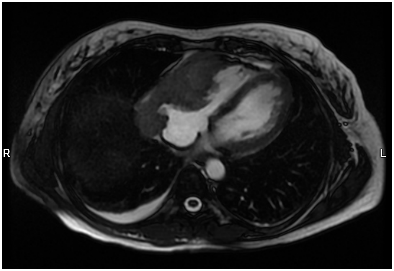

A pericardial catheter was placed and a large bloody effusion was drained. A cardiac MRI (Figure 1B) revealed a 10 cm infiltrating soft tissue mass involving the right atrium and right ventricle. The right coronary artery was encased and attenuated. The mass extended into the atrioventricular groove and infiltrated the roof of the right ventricle. The anterior surface of the aortic root was also encased. Heterogeneous enhancement of the mass suggested a vascular lesion suggestive of angiosarcoma.

Figure 1B Cardiac MRI shows an infiltrating soft tissue mass involving the right atrium and right ventricle.